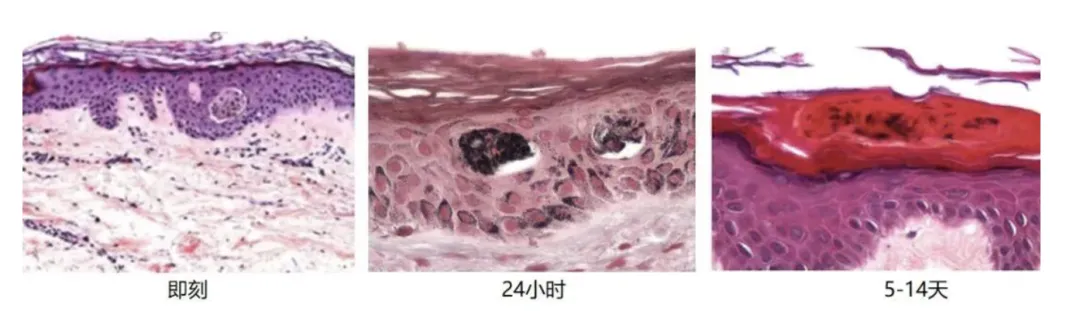

首先,在物理层面上,将已有的黑色素颗粒“震”成细沙;其次,激光的热能会释放特定信号,定向唤醒皮肤里的巨噬细胞(CD163+),加速吞噬并运走这些被震碎的色素。而且比较让人惊喜的是,研究发现特定的激光模式还能抑制黑色素生成,下调酪氨酸酶的表达。

Western blot结果表明,在激光处理后酪氨酸酶Tyrosinase蛋白表达在第7天明显下调,并且这种抑制状态一直持续到第 30 天。

简单说就是👉激光不仅能粉碎已经产生的黑色素,还能减缓后续变黑的速度,起到更持久的美白作用。